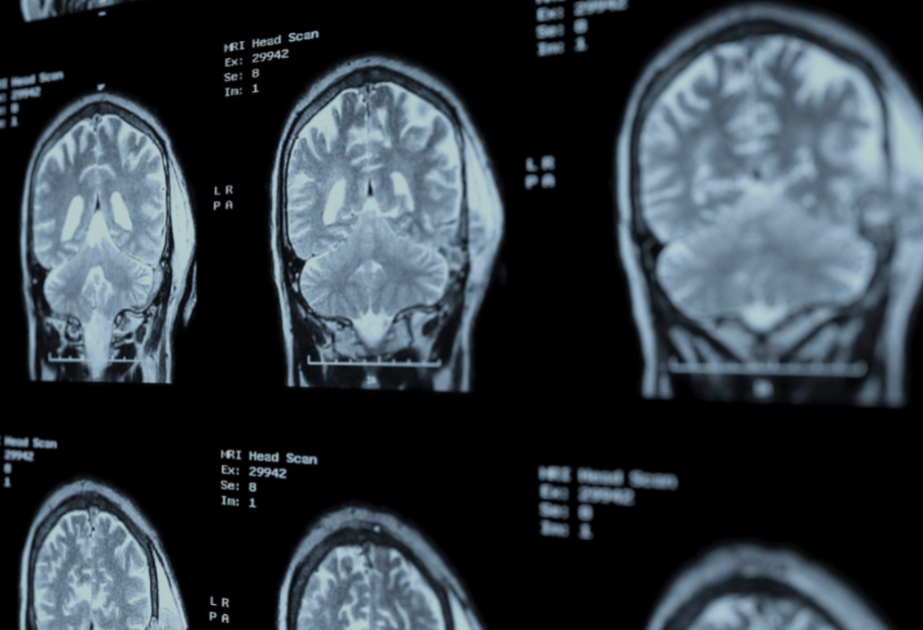

Bugun.tv “Independent”ə istinadla xəbər verir ki, bu nəticələr Altsheymer xəstəliyinə qarşı dərmansız müalicə yanaşmasının mümkün ola biləcəyini göstərir. Söhbət nikotinamiddən (B3 vitamini forması) və epiqallokatexin qallatdan, yəni yaşıl çayın tərkibində olan güclü antioksidantdan gedir. Tədqiqat zamanı bu maddələrin sinir hüceyrələrində enerji istehsalı üçün əsas molekul olan GTP səviyyəsini bərpa etdiyi aşkarlanıb. Müşahidələr göstərib ki, qocalmış sinir hüceyrələrinin bu maddələrlə 24 saat ərzində müalicəsi nəticəsində GTP səviyyəsi gənc hüceyrələrdəki normal göstəricilərə qayıdır. Enerji balansının bərpası isə neyronların özünü təmizləmə funksiyasını aktivləşdirərək, Altsheymerin əsas əlamətlərindən biri sayılan amiloid zülal yığıntılarının əhəmiyyətli dərəcədə azalmasına səbəb olur.